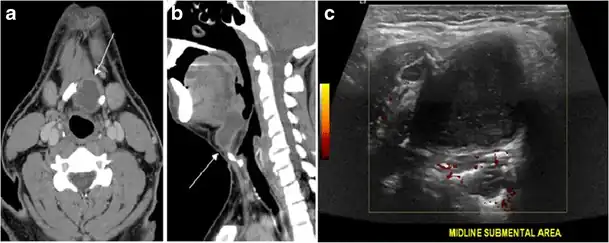

Fig. 13. A 27-year-old female patient known to have goiter. a, b Axial and sagittal enhanced CT scan images of the neck demonstrate a heterogeneously enhancing, enlarged thyroid gland with scattered calcifications (white arrow), cystic changes, and substantial retro-sternal extension (black asterisks). No lymphadenopathy or substantial airway narrowing.[1]

Fig. 14. A 19-year-old male patient known to have multi-nodular goiter and FNA, showing underlying Hashimoto's thyroiditis. a, b Sagittal and transverse greyscale and colour Doppler ultrasound of the neck demonstrate a hypoechoic enlarged right thyroid lobe with small hyperechoic regenerative nodules and marked hypervascularity (white arrows). c, d Enhanced axial CT scan images of the neck demonstrate a heterogeneously enhancing and enlarged thyroid gland, left more than right lobe, and the trachea is markedly narrowed.[1]